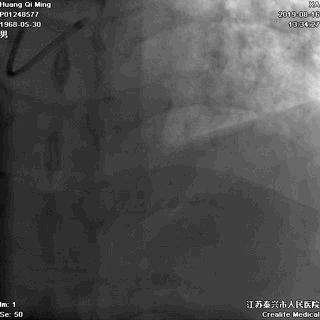

LCX植入后即刻效果满意

LCX近中段病变,狭窄最重达90%

LCX,PTCA+DES;